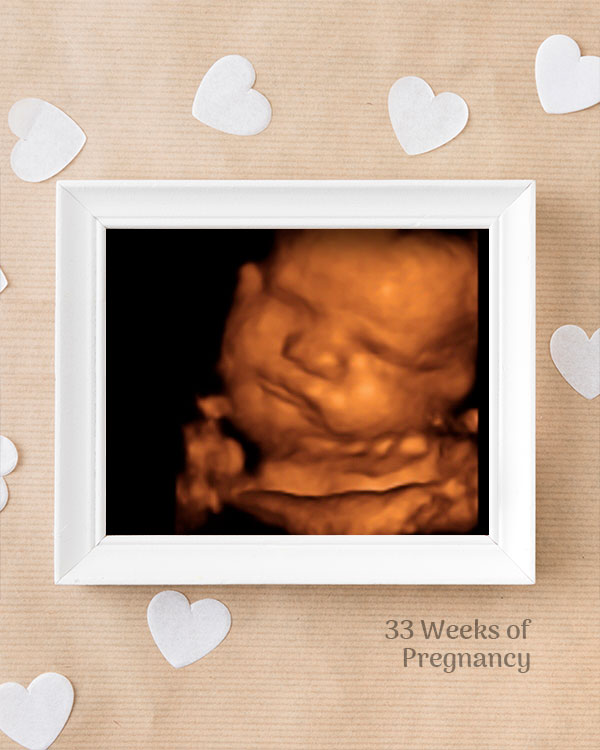

3D / 4D Baby Scan

Mediserv Diagnostics pioneered 4D scanning in the Malabar region. These advanced scans provide realistic images of the baby, allowing detailed evaluation of fetal structures and movements while creating a meaningful bonding experience for parents.